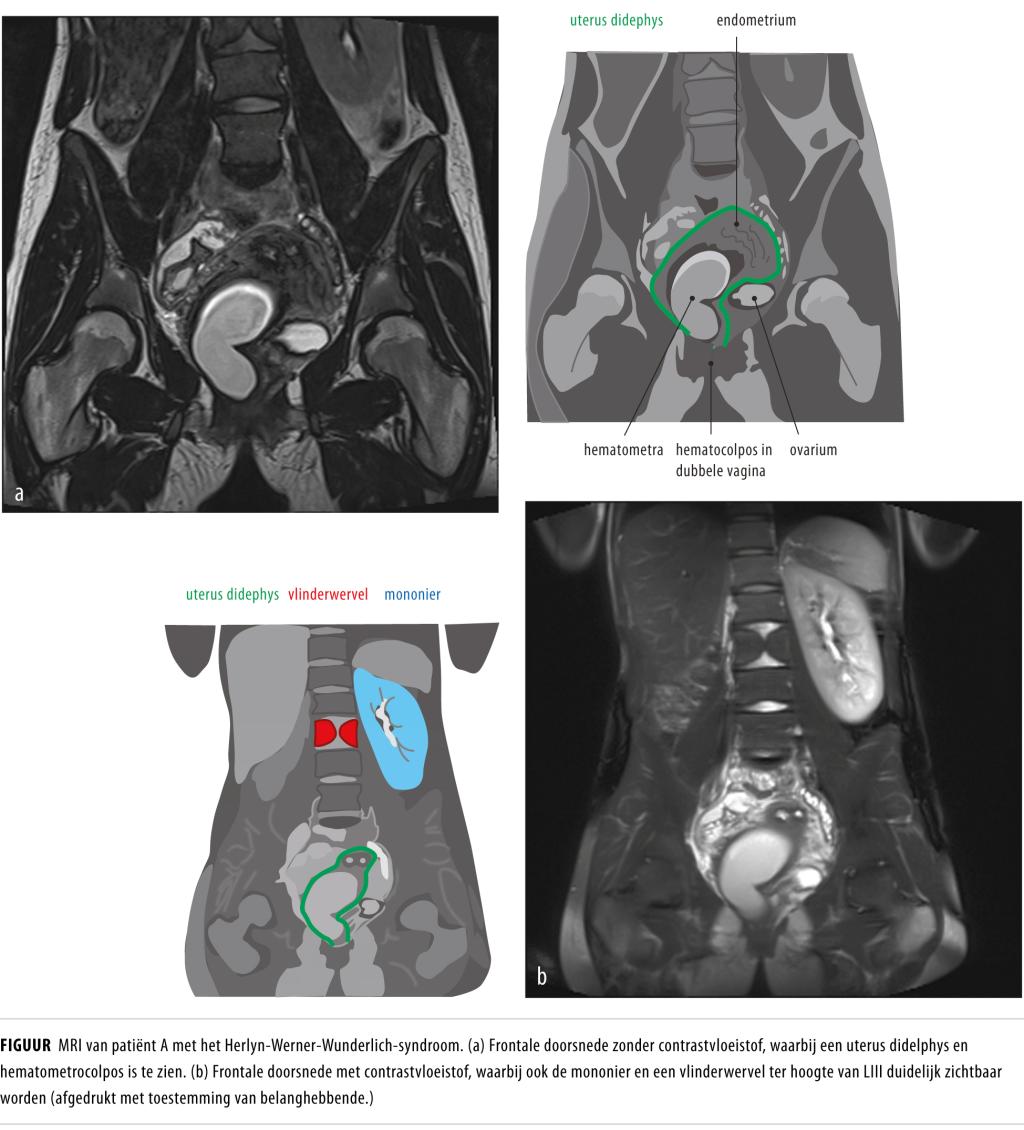

In de verklarende tekeningen bij de figuur waren anatomische structuren en afwijkingen niet correct aangegeven. Onderstaande figuur vervangt het figuur bij artikel A7886.

Op de Spoedeisende Hulp worden veel patiënten gezien met een acute buik. Een minder bekende oorzaak hiervan is het Herlyn-Werner-Wunderlich-syndroom. Dit kenmerkt zich door een uterus didelphys, een geobstrueerde hemivagina en een ipsilaterale nieragenesie of -dysplasie.

Wij zagen een 16-jarige vrouw met progressieve buikklachten en een nier- en anusafwijking in de voorgeschiedenis. Vanwege zowel druk- als loslaatpijn rechts onder in de buik en een verhoogde CRP-concentratie dachten we aan appendicitis acuta. Bij abdominale echografie zagen we een cysteuze structuur, vermoedelijk van ovariële of tubaire origine. Patiënte onderging een spoedlaparoscopie vanwege verdenking op een ovariumtorsie. Hierbij werd een uterus didelphys gezien met een afwijkend rechter systeem. Aanvullende diagnostiek met een MRI-scan toonde afwijkingen passend bij Herlyn-Werner-Wunderlich-syndroom.